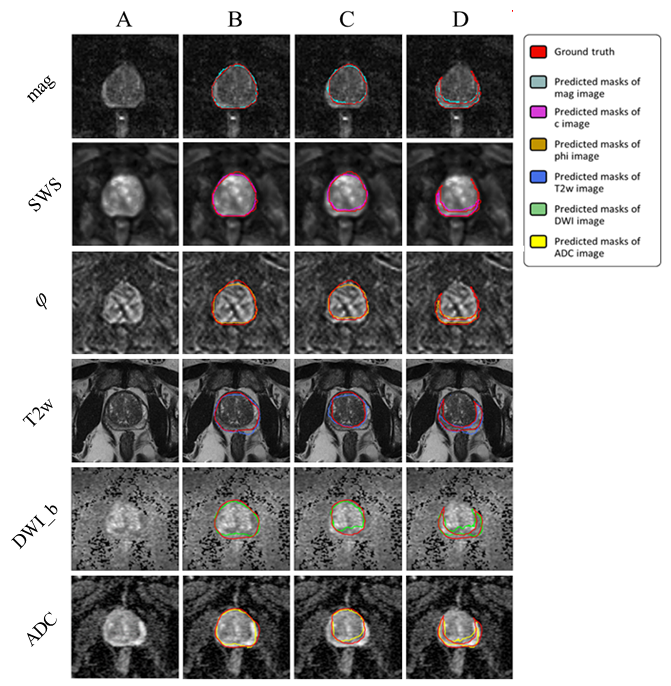

Figure 5 and Figure 6 illustrate segmentation results for each of the two training approaches. The boundary of automatically segmented regions closely follows the boundary of manual segmentations.

Figure 5: Examples of segmentation results achieved with IMs: first column (A) shows the original image, second (B), third (C) and forth column (D) show masks of prostate, central and peripheral zones, respectively.

Figure 6: Examples of segmentation results achieved with the UM: first column (A) shows the original image, second (B), third (C) and forth column (D) show masks of prostate, central and peripheral zones, respectively.

Our experimental results for IMs trained on different combinations of maps showed that the proposed method was capable of efficiently segmenting PG, CZ, and PZ from the input MRI/MRE images. DS ranged from 0.87±0.04 (ADC) to 0.93±0.04 (mag), from 0.85±0.09 (DWI_b) to 0.95±0.03 (mag), and from 0.53±0.10 (ADC+DWI_b) to 0.77±0.05 (mag), for PG, CZ, and PZ, respectively. Also, HD was minimized (i.e., best contour consistency) based on mag with 0.86, 0.76, 0.98 mm (Figure 5 and Table 2). However, performance differences between MRE (mag, SWS, φ𝜑\varphi) and MRI maps (T2w, DWI_b, ADC) were statistically not significant except for CZ, where MRE (mag, SWS, φ𝜑\varphi) had a significantly higher DS than MRI (T2w, DWI_b, ADC, p<0.05).

Unlike IMs, the UM can process any map or combination of maps, which facilitates clinical applications. Compared with IMs, the UM had higher DS in PG and CZ and lower DS in PZ. Assessed for different prostate zones, DS of the UM ranged from 0.77±0.11 (DWI_b) to 0.92±0.04 (mag, SWS, φ𝜑\varphi), from 0.65±0.08 (DWI_b) to 0.86±0.06 (mag, SWS, φ𝜑\varphi), and from 0.28±0.10 (DWI_b) to 0.57±0.05 (mag), for PG, CZ, and PZ, respectively. The smallest HD of 1.15, 1.45, and 1.81 for PG, CZ, and PZ, respectively, was found for mag. Images are presented in Figure 6, and the results are summarized in Table 3.

Unlike IMs, the UM showed a significantly higher DS when using MRE data in comparison with MRI data (p < 0.001, 0.05, and 0.05 for PG, CZ, and PZ, respectively). Overall, IMs had significantly more accurate results compared with the UM in terms of both DS and HD with p-values < 0.01 for PG, CZ, and PZ. This is shown in Figure 7, illustrating that DS was higher and HD lower for IMs than for the UM. Figure 8 shows a case where model segmentations were inaccurate compared with the ground-truth masks. Quantitative analysis, for both IMs and the UM, of pixel values in PG, CZ, and PZ showed no significant difference (p>0.05) between ground-truth and automated prostate segmentation. Group mean values are presented in Table 4 and Table 5.

Our results show that IMs performed excellent across all maps and sequences with high values for DS and low values for HD. In our experiments, segmentation was most reliable when we used T2w and MRE magnitude images, which provide sufficiently rich anatomical details for automated prostate segmentation while quantitative parameter maps such as SWS, φ𝜑\varphi and ADC lack those details. Figure 9 depicts a variety of maps in a patient demonstrating that anatomy of prostate boundaries is well preserved on T2w and MRE magnitude images while it is less clearly visible on ADC, DWI_b, SWS and φ𝜑\varphi maps.